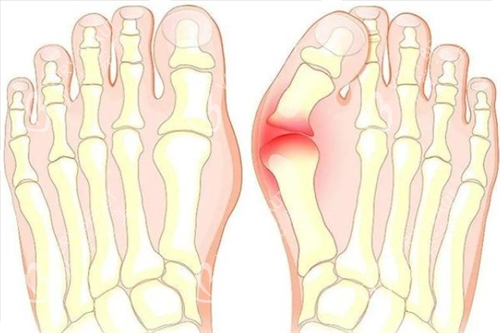

在追求美丽与健康的道路上,大脚骨问题成为了许多人的困扰。它不仅影响足部美观,还可能引发疼痛与功能障碍。北京广济医院凭借其在大脚骨治疗领域的卓然表现,成为了众多患者的信赖之选。下面,让我们深入了解一下这家医院。

医院重视患者的个体差异,针对不同病情和体质的患者,制定个性化的治疗方案。对于轻度外翻患者,可能建议采用支具调整结合改善训练;而中重度患者则需通过手术矫正骨骼和软组织平衡。这种个性化的治疗方案满足了患者的需求,确保了手术结果的满意度和自然度。